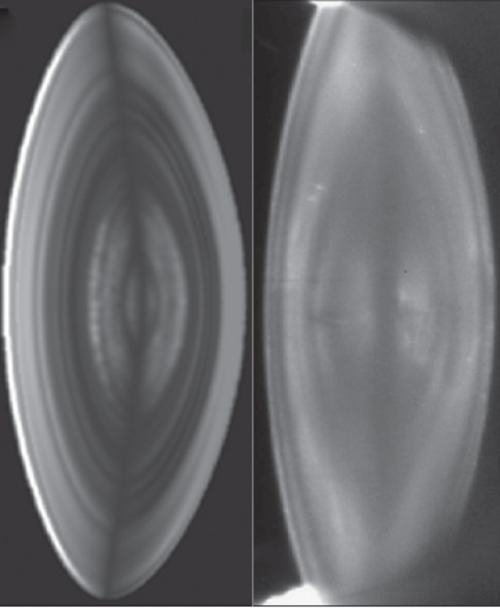

Figure 2: A) Simulated image constructed of reflected and scattered light using a model with the refractive index profile of a 35-year-old lens measured using Talbot interferometry. B) Slit-lamp image of a 28-year-old lens [12].

The light that was refracted through the model lens underwent reflection and scatter when it encountered a fluctuation in the gradient. The resulting image closely resembled the view seen when looking into a living eye [12] (Figure 2). The zones of discontinuity could be explained as caused by the fluctuations in the refractive index gradient [11]. This, however, does not explain why such fluctuations occur. They may be linked to growth stages, rather like is found with the rings of a tree, which indicate spurts and halts in growth rate. If this were to be the case and the zones of discontinuity were manifestations of changes in growth and development, these characteristic markings would be more than just interesting features with little clinical relevance but rather offer an excellent perspective on the growth and potentially ageing processes in the lens and also systemically. If more were known about the zones of discontinuity, clinicians could monitor how these characteristics alter with time and in response to various medications or disease states.